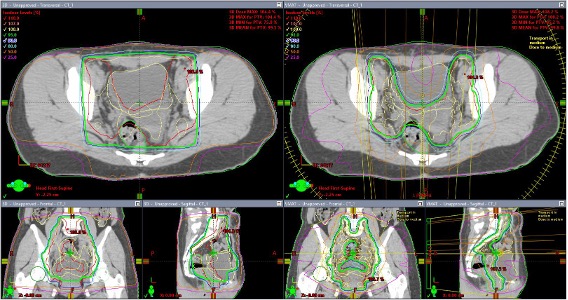

4門照射(図ひだり)とIMRT(図みぎ)による全骨盤照射の線量分布の比較

IMRTにより小腸、膀胱、直腸線量を低減できる - 呼吸同期照射